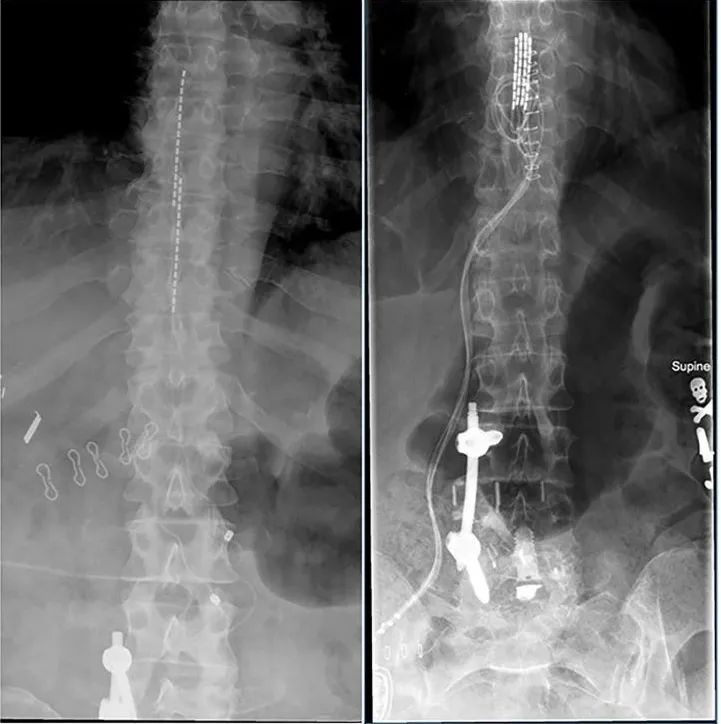

2. 经皮椎体强化技术

晚期肺癌常发生骨转移,尤其是脊柱转移,可能导致椎体压缩性骨折(VCF)和剧烈疼痛。经皮椎体强化技术通过向受损椎体内注入“骨水泥”来稳定椎体、缓解疼痛。

- 经皮椎体成形术(PVP): 直接向病变椎体注入骨水泥,操作相对简单快速。

- 球囊扩张椎体后凸成形术(PKP): 先用球囊扩张被压缩的椎体,形成空腔后再注入骨水泥,有助于恢复椎体高度和改善脊柱稳定性。

PVP和PKP的选择需根据患者具体情况(如椎体压缩程度、是否需要恢复高度、经济条件等)决定。下表总结了两者的主要区别: